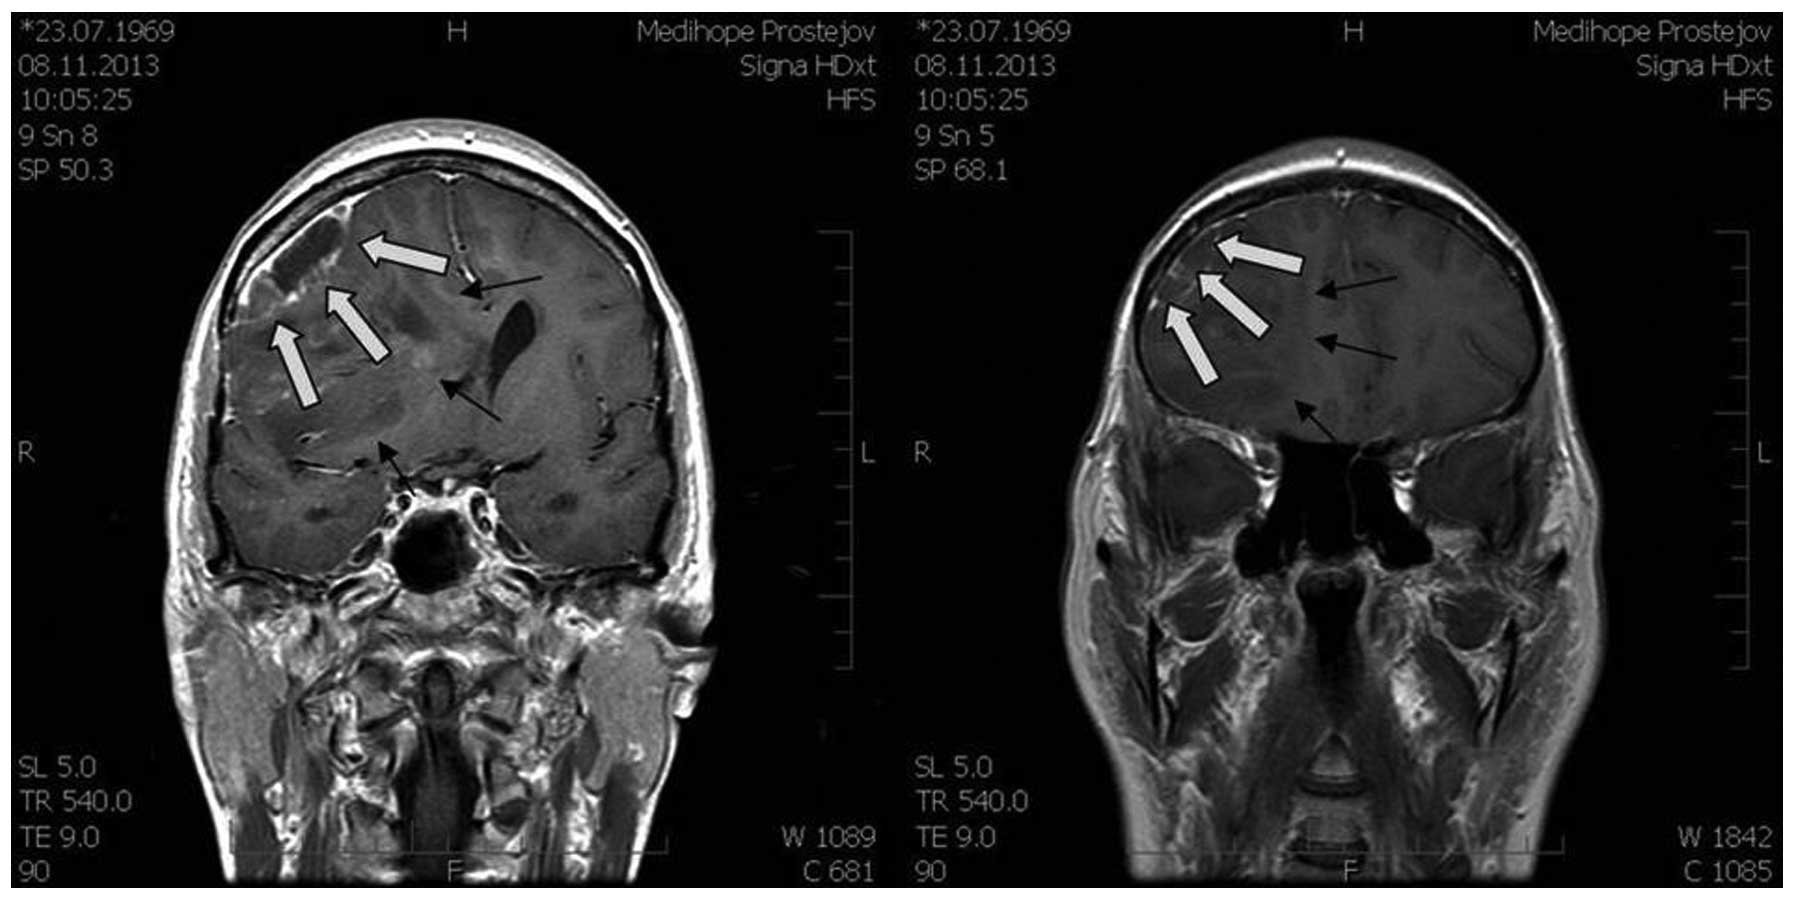

A 44-year-old female patient was examined in the Department of Neurosurgery (Third Faculty of Medicine, Charles University in Prague and University Hospital Kralovske Vinohrady in Prague, Prague, Czech Republic) for headaches that were prominent for 2 months. Headaches were of an increasing intensity and a magnetic resonance imaging (MRI) scan (Figs. 1 and 2) showed a large expansive process in the right frontal lobe (81×70×76 mm), with the pressure on midline brain structures and compression of the ventricular system. The MRI scan indicated a glioma. Neurological examination revealed light left-sided hemiparesis.

Figure 1.

Preoperative magnetic resonance imaging axial scan (high- and area low-grade areas).

Figure 2.

Preoperative magnetic resonance imaging coronal scan (high- and area low-grade areas).